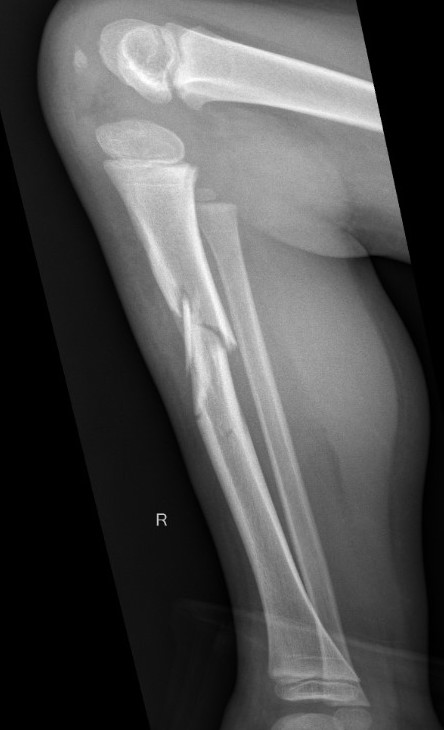

Proximal Metaphyseal Tibial Fracture / Cozen's Fracture

Issue

- may develop long term valgus alignment

- due to medial epiphyseal overgrowth / periosteum medially